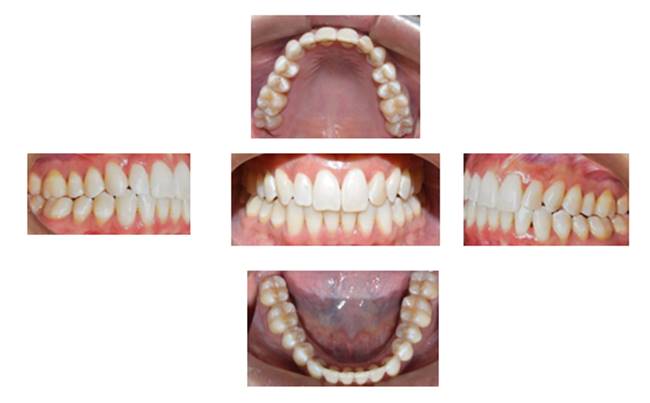

Methods: The clinical examination included extra-oral and intra-oral photographs, panoramic radiographic, lateral cephalometric, stone casts, and upper and lower arch analysis obtained from ClinCheck 3.0.The treatment planning was resolved the crowding in both upper and lower arches and the severe rotation of 33 tooth (46°) using Invisalign system as well as the canine and molar relationship, dental verticalization, adequate over jet, overbite and dental midline using the same system. The duration of the treatment was approximately eight months.

Results: In Post-treatment extra oralphotographs, no significant changes were observed at the end of the treatment. Intraoral photographs showed an important and notable improved aesthetics. The canine relationship improved slightly and molar Class Irelationship was maintained. An increase in transverse diameter was observed at the level of first premolars, second premolars and first molars. The overbite was improved. The crowding and the severe canine rotation were corrected. No obvious root resorption was radiographically evident and slight cephalometric changes.